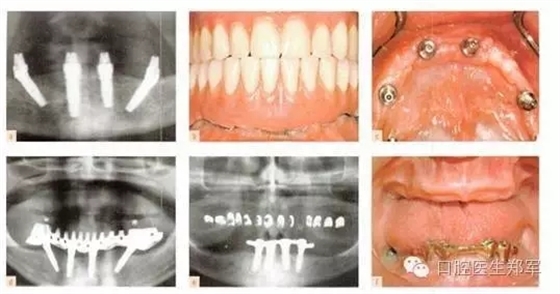

剩余牙槽骨的客觀解剖因素決定是否可以放置全牙弓種植體。在上頜骨,上頜竇提升通常是一個選擇,但是可能會導(dǎo)致極高的牙冠長度和不協(xié)調(diào)的冠根比。所謂“All on Four”,四個種植體支持式固定修復(fù)一直存在爭議,支持者和懷疑者都在等待長期的研究結(jié)果(圖3和4)。下頜后牙種植體的位置是由剩余牙槽嵴寬度和高度,以及不可預(yù)知的垂直方向上骨增量共同限制。5年的研究結(jié)果表明,種植體的存活和成功不受修復(fù)類型的影響。

圖3下頜的治療選擇。a到d 固定“All on Four”修復(fù)和遠(yuǎn)中傾斜植入。(圖片由Dr. B Marshak提供)。e 和f 由四個種植體支撐的下頜覆蓋義齒。 |

圖4 種植支持的覆蓋義齒或4個傾斜種植體支持的固定種植體支持式的修復(fù)。“All on Four”已經(jīng)廣泛的傳播,懷疑者等待更可靠的證據(jù)結(jié)果。臨床圖像由Dr. B Marshak提供。 |